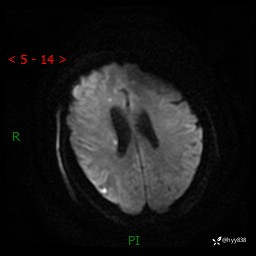

患者性别:女

患者年龄:57岁

简要病史:昏迷入院

颅脑MRI(T2WI+DWI)